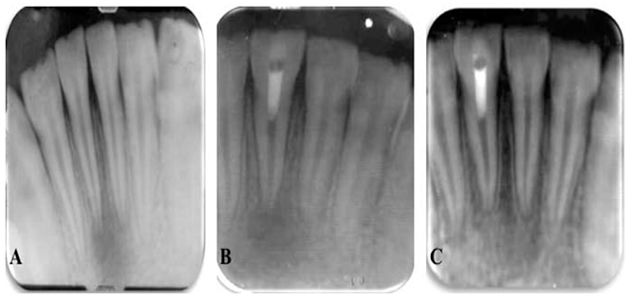

Regenerative Endodontics:Revascularization

Regenerative endodontics is one of the most exciting developments in dentistry today and endodontists are at the forefront of this cutting-edge research. Regenerative endodontics uses the concept of tissue engineering to restore the root canals to a healthy state, allowing for continued development of the root and surrounding tissue. Endodontists’ knowledge in the fields of pulp biology, dental trauma and tissue engineering can be applied to deliver biologically based regenerative endodontic treatment of necrotic immature permanent teeth resulting in continued root development, increased thickness in the dentinal walls and apical closure. These developments in regeneration of a functional pulp-dentin complex have a promising impact on efforts to retain the natural dentition, the ultimate goal of endodontic treatment. Learn More >